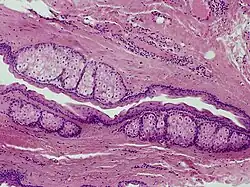

Steatocystoma multiplex is a benign, autosomal dominant congenital condition resulting in multiple cysts on a person's body. Steatocystoma simplex is the solitary counterpart to steatocystoma multiplex.[2]

The cysts are mostly small (2–20 mm) but they may be several centimetres in diameter. They tend to be soft to firm semi-translucent bumps, and contain an oily, yellow liquid. Sometimes a small central punctum can be identified and they may contain one or more hairs (eruptive vellus hair cysts). They may become inflamed and heal with scarring, like acne nodules (see nodulocystic acne and hidradenitis suppurativa).

Steatocystomas are thought to come from an abnormal lining of the passageway to the oil glands (sebaceous duct).